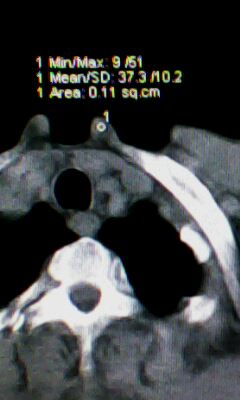

胰尾部占位?

未见明显异常。“胰尾占位”为肠管